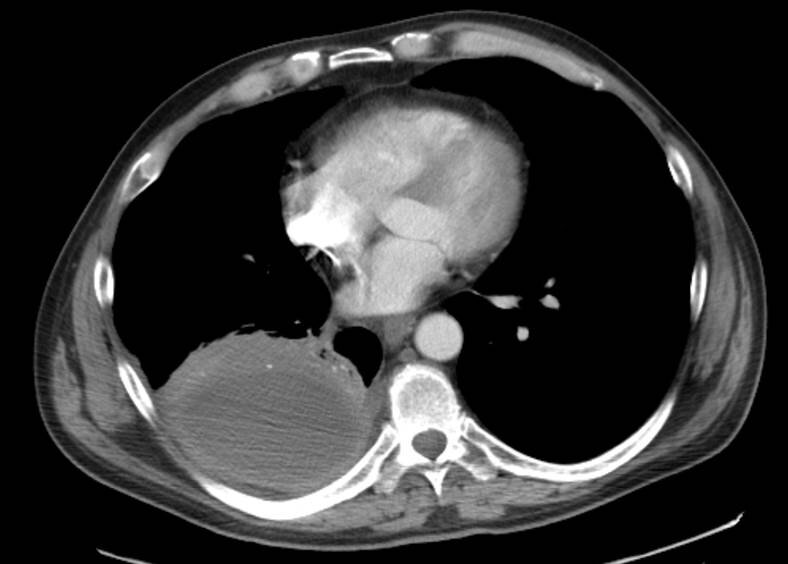

A 48-year-old man is hospitalized following 4 weeks of cough and fever unresponsive to antibiotic therapy.

Chest CT scan is shown.

Which of the following is the most likely diagnosis?

Empyema

Lung abscess

Lung cancer

Mesothelioma